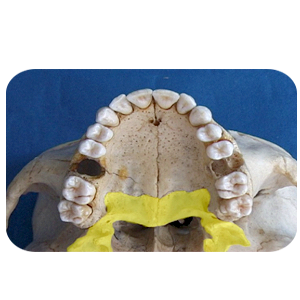

Units of the Department of Forensic Medicine and Clinical Toxicology Head of the Department's Message Services Units Academic Staff Course Description The department has the following devices and samples: